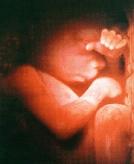

受精后6星期,人形已隐约可见。这时,胚胎的心跳每分钟140—150下.是母亲心跳的两倍。

我这个时候的样子和小猪、小猫、小狗的胎儿没多大差别。